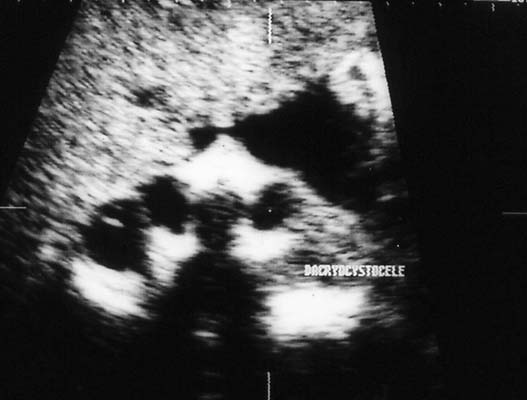

Dacryocystocèle